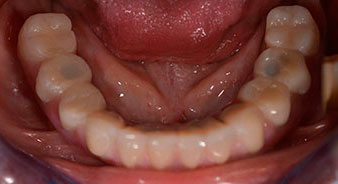

L'empreinte et l'enregistrement de l'occlusion ont ensuite été effectués afin que le prothésiste dentaire puisse commencer à réaliser la restauration provisoire. Celle-ci a été vissée le jour même (Fig. 17 et 18).

Implants

Fig. 17

Fig. 18